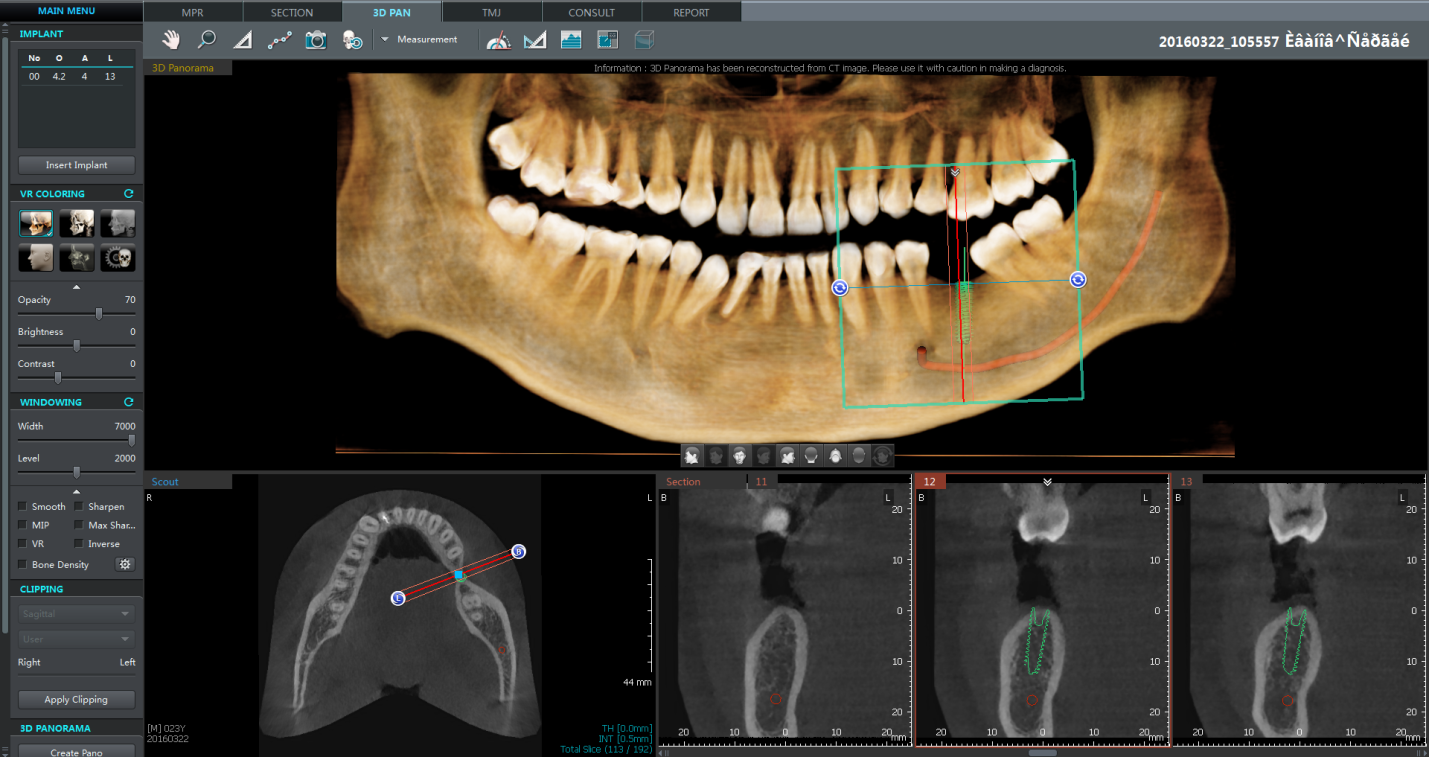

Согласно российскому законодательству судьи освобождены от необходимости утверждать свое мнение в том, в чем они не являются специалистами. Для этих целей предусмотрена судебно-медицинская экспертиза. Эксперты назначаются по требованию сторон или по инициативе судьи (ст. 74 и 78 гражданско-процессуального кодекса и ст. 184, 194 уголовно-процессуального кодекса). Учитывая возмездный характер отношений врача и пациента при дентальной имплантации, выводы судебно-медицинских экспертов должны опираться на оценку осложнений метода. Осложнения хирургического этапа дентальной имплантации применительно к возможным юридическим последствиям наиболее опасны. В этой связи эти осложнения следует рассматривать в зависимости от того, на каком этапе хирургического лечения они возникли: в период подготовительных хирургических манипуляций в области предполагаемой дентальной имплантации, во время хирургического этапа дентальной имплантации, в ранние сроки после дентальной имплантации (до снятия швов или заживления раны вторичным натяжением), при проведении второго этапа имплантации (через 3-6 месяцев после дентальной имплантации), в отдаленные сроки (спустя 5 лет и более) после дентальной имплантации. Необходимо помнить, что по современным нормативам предоперационные этапы должны быть подкреплены данными 3D-томографии, которые обязательно учитываются при подборе имплантатов и костнопластических материалов. Вариантов программного обеспечения для планирования дентальной имплантации множество. В последнее время особо следует отметить ряд преимуществ приложения Ez3D-i V4.3.0 от Vatech. Простота и легкость в интерпретации трехмерного изображения помогает стоматологу сориентироваться в режиме MPR, четко сфокусировать объект исследования, провести точные измерения в планируемом сегменте имплантации, промаркировать нижнечелюстной канал, провести диагностику дополнительных ответвлений (добавочные каналы Робинзона), визуализировать объем верхнечелюстных пазух, виртуально позиционировать имплантаты любой фирмы, измерить оптическую плотность костной ткани в зоне планируемой имплантации в системе HU (Рис.1). Также с Ez3D-i V4.3.0 стало возможно создать заготовку для создания хирургического шаблона под последующую обработку.

Рис.1 3D-панорама Ez3D-i V4.3.0, виртуальная установка дентального имплантата в область отсутствующего 46 зуба.